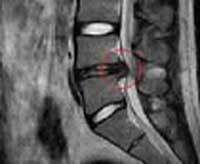

qa18_01